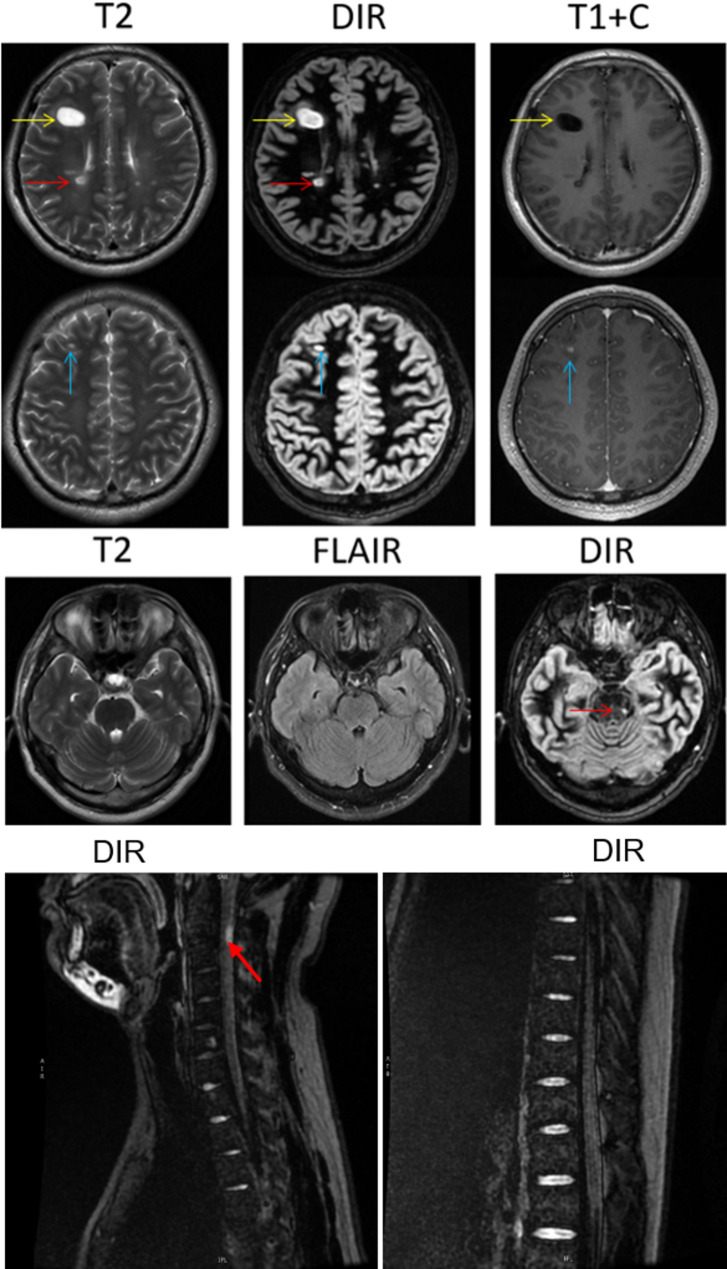

Use of MRI-double inversion recovery sequence for early diagnosis of multiple sclerosis: case series.